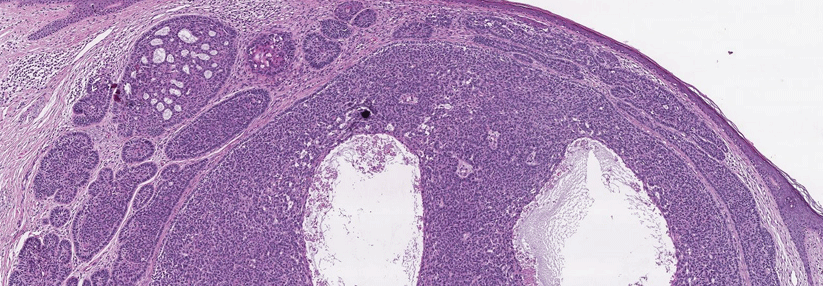

Das Basaliom ist der häufigste maligne Tumor des Menschen, Inzidenz steigend. Therapeutisch gilt nach wie vor die Exzision als der Goldstandard. Dank vielfältiger Therapieoptionen stellen auch fortgeschrittene und metastasierte Tumoren heute keine ausweglose Situation mehr dar.

Typisch für das Basaliom ist ein langsames, lokal destruierendes Wachstum. Eine Meta­stasierung kommt vor, ist aber sehr selten. Das polymorphe Erscheinungsbild der Tumoren reicht von Ulzerationen, ekzematösen und narbigen Läsionen bis zu zystischen Veränderungen, schreiben Dr. ­Manuel ­Krieter und Prof. Dr. ­Erwin ­Schultz von der Klinik für Dermatologie der Medizinischen Privatuniversität Nürnberg. Basalzellkarzinome entwickeln sich nur in Arealen, die Haarfollikel ausbilden, nicht an Schleimhäuten, Handflächen oder Fußsohlen.